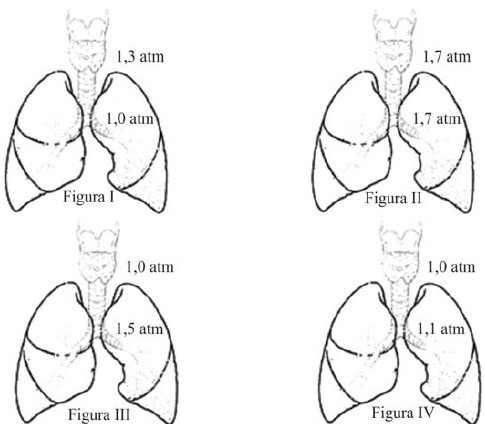

Abaixo, está representado um ciclo de ventilação pulmonar idealizado. Durante o início da inspiração, a pressão do gás dentro dos pulmões é mínima, havendo acréscimo da pressão interna e do volume com a entrada de ar. Assim que o pulmão está em sua capacidade máxima, há um período curto de pausa, em que trocas gasosas são realizadas a um volume constante, o que reduz a pressão. A pressão interna começa a decrescer à medida que há esvaziamento parcial da câmara, e atinge pressão mínima.

Internet: <www.livemedical.net/respiratory-mechanics> (com adaptações).

Entre as opções a seguir, assinale a que melhor representa o ciclo de ventilação descrito acima.

O pulmão é o órgão do corpo humano responsável pelas trocas gasosas entre o ambiente e o sangue. Nas figuras de I a IV, a seguir, está ilustrado um mesmo pulmão em quatro situações diferentes. As figuras mostram, ainda, as pressões internas e externas a que o pulmão está submetido nessas quatro situações.

Considerando essas informações, conclui-se, após os cálculos, que o módulo da força resultante nas paredes do pulmão está representado, como máximo e mínimo, respectivamente, nas figuras